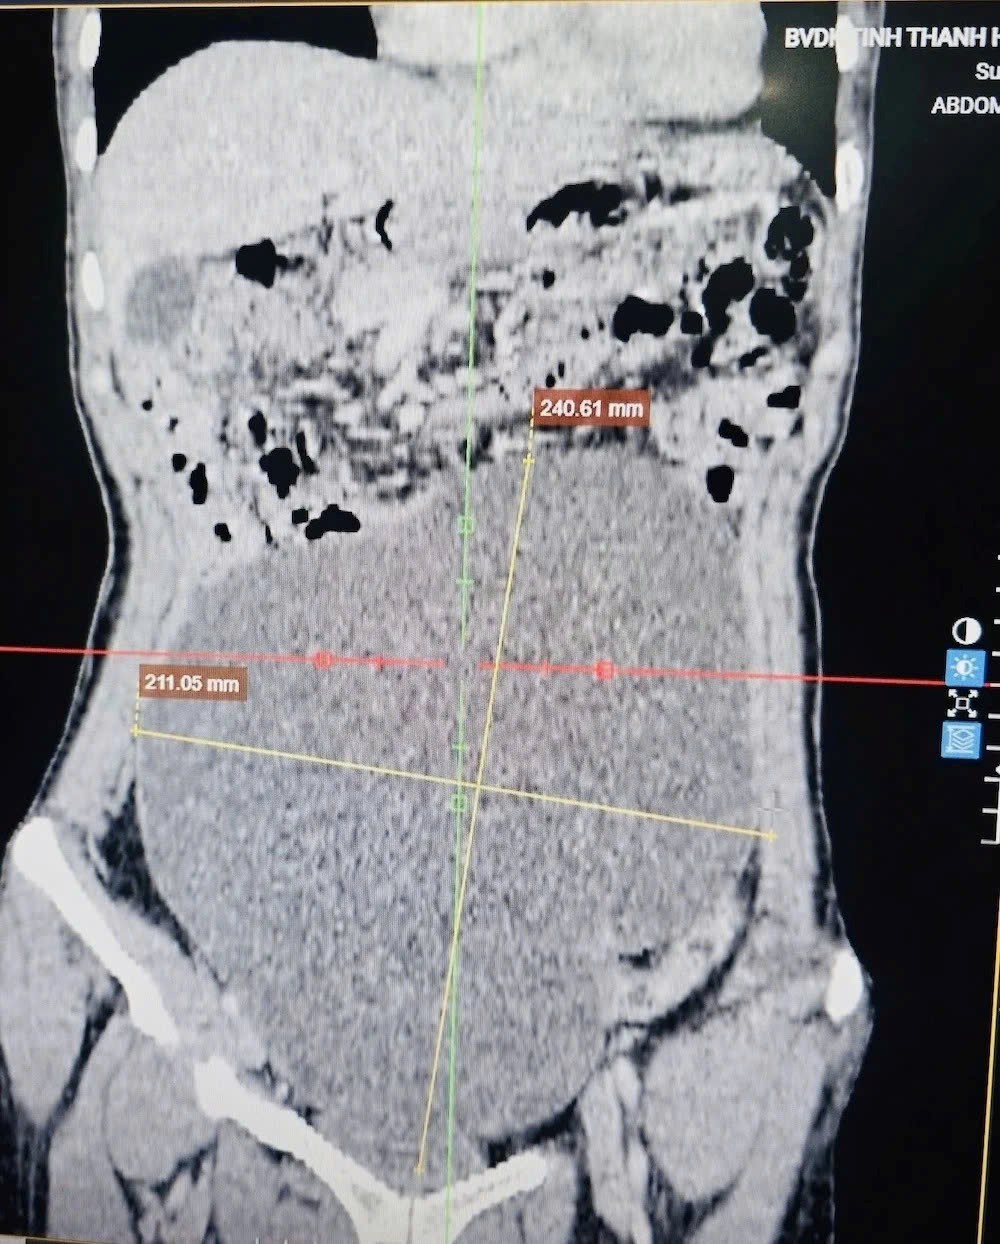

Qua thăm khám lâm sàng và thực hiện các xét nghiệm cận lâm sàng, đặc biệt là chụp cắt lớp vi tính ổ bụng, các bác sĩ phát hiện một khối u rất lớn, chiếm gần toàn bộ ổ bụng, kéo dài từ hạ vị lên thượng vị, xuất phát từ buồng trứng, có dấu hiệu theo dõi ác tính.

Ca mổ do Khoa Ngoại tổng hợp 2 phối hợp với Khoa Gây mê hồi sức thực hiện. Ê-kíp phẫu thuật đã bóc tách thành công khối u xuất phát từ buồng trứng trái, kích thước khoảng 25cm, nặng gần 3kg. Mẫu bệnh phẩm sau đó được gửi làm xét nghiệm mô bệnh học.